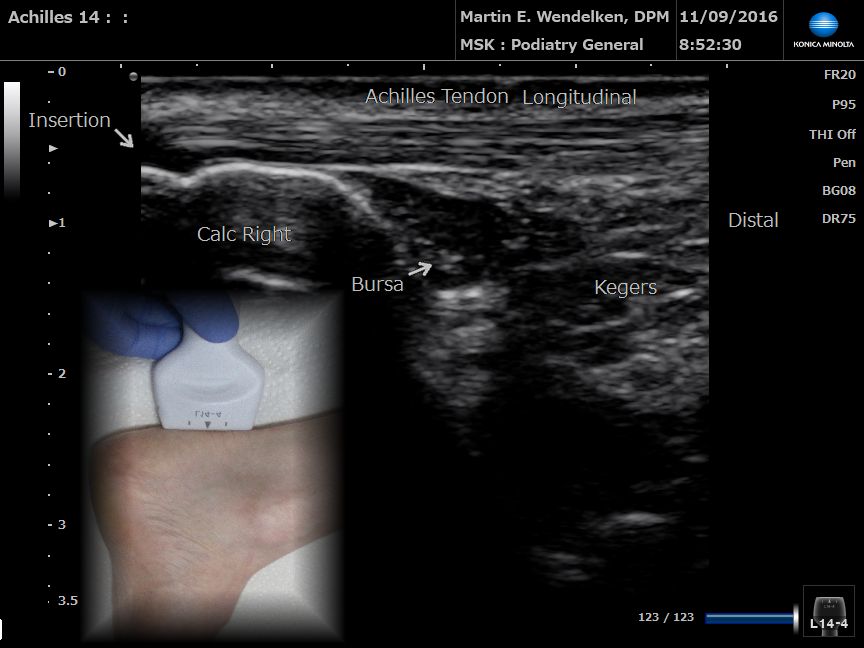

• Image 2: Achilles Tendon